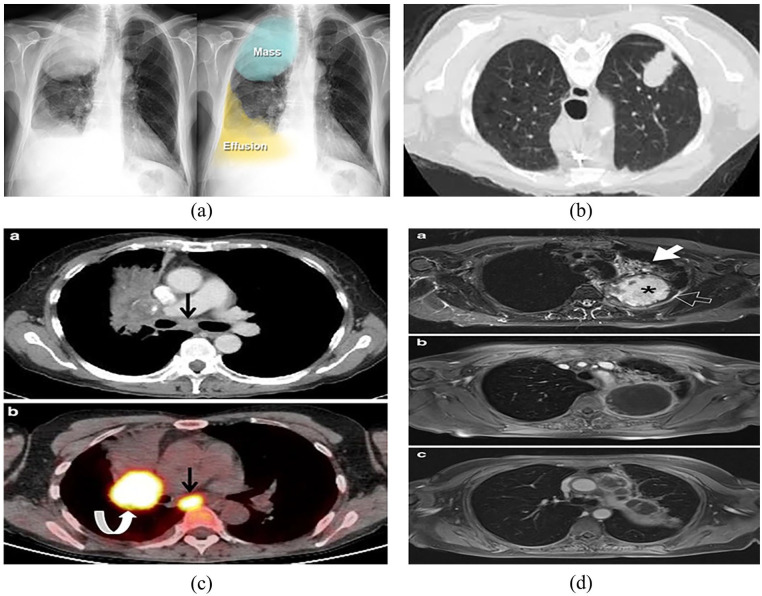

Image-based diagnosis has become a crucial tool in the identification and management of various cancers, particularly lung and colon cancer. This review delves into the latest advancements and ongoing challenges in the field, with a focus on deep learning, machine learning, and image processing techniques applied to X-rays, CT scans, and histopathological images. Significant progress has been made in imaging technologies like computed tomography (CT), magnetic resonance imaging (MRI), and positron emission tomography (PET), which, when combined with machine learning and artificial intelligence (AI) methodologies, have greatly enhanced the accuracy of cancer detection and characterization. These advances have enabled early detection, more precise tumor localization, personalized treatment plans, and overall improved patient outcomes. However, despite these improvements, challenges persist. Variability in image interpretation, the lack of standardized diagnostic protocols, unequal access to advanced imaging technologies, and concerns over data privacy and security within AI-based systems remain major obstacles. Furthermore, integrating imaging data with broader clinical information is crucial to achieving a more comprehensive approach to cancer diagnosis and treatment. This review provides valuable insights into the recent developments and challenges in image-based diagnosis for lung and colon cancers, underscoring both the remarkable progress and the hurdles that still need to be overcome to optimize cancer care.